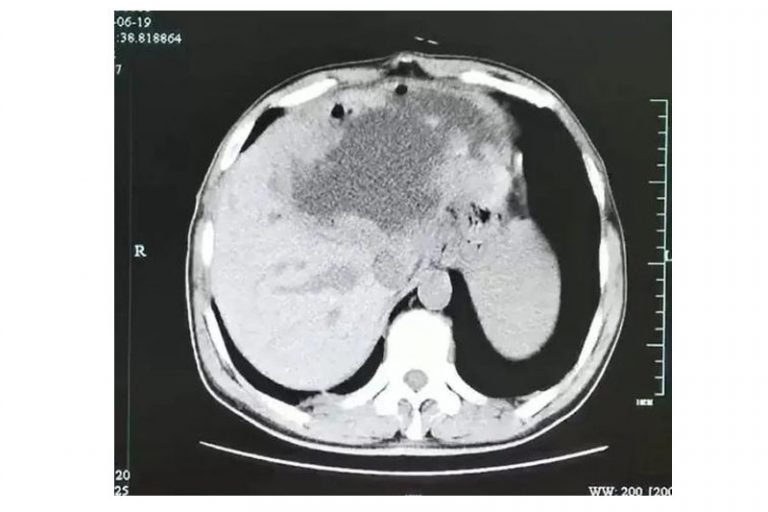

綜合內地報道,一名55歲的謝姓男子,在杭州打工多年,早前因父親父親病故回鄉,不久後開始出現食慾不振、乏力,起初還伴隨輕度腹痛、腹瀉。相隔4個月,直到連續出現3日畏寒、發熱,隨即杭州市第一人民醫院肝膽胰外科求醫。醫生檢查竟發現謝男的左肝已被吃光,甚至變成一個大膿球,達長19厘米,寬18厘米,深12厘米的大小,而且囊壁上還長有很多腫瘤,壁亦很厚。

接著,醫生以穿刺引流,將大量的灰白色膿液引出,又再過了三星期,謝男的左肝膿腫小了一大半,可是肝臟上仍有腫瘤,於是醫生決定進行手術將左半肝切除,豈料手術期間發現膿腫壁上大量的腫瘤樣結構,竟然是肉芽腫性炎性腫塊,而內裡還爬滿無數燈泡狀、殼厚的華支睾吸蟲蟲卵。